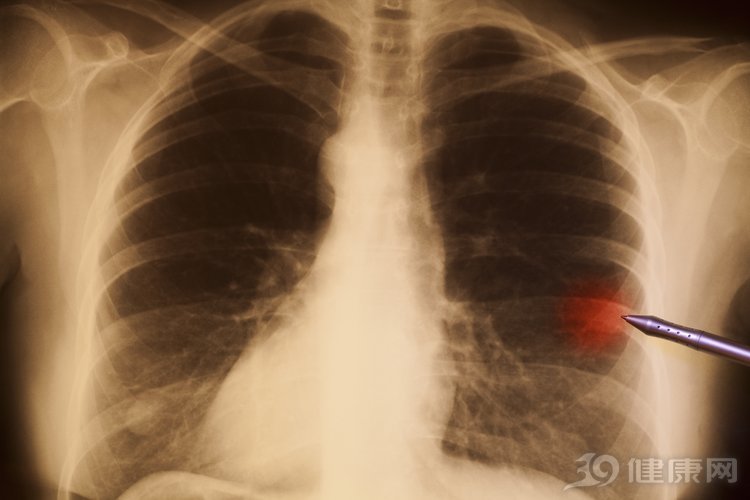

肺癌是世界上最常见的癌症,也是我国目前第一大癌。数据显示,我国每年新发肺癌患者约78.1万,因罹患肺癌而死亡的患者约62.6万,均居恶性肿瘤首位。